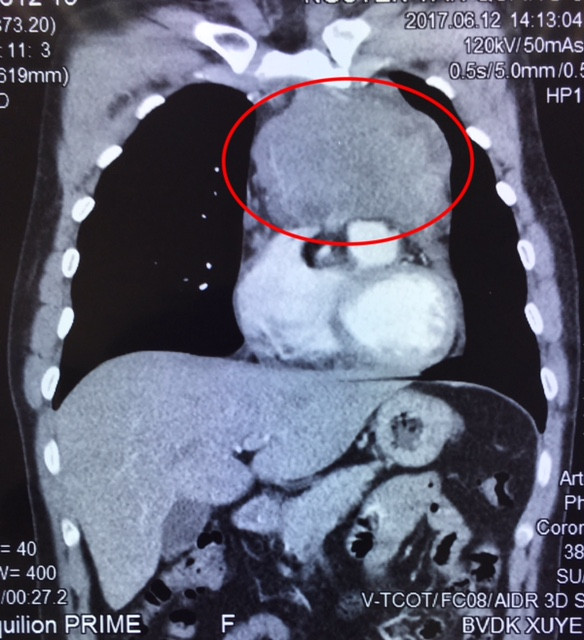

BN Q. có triệu chứng ho dai dẳng, tức ngực liên tục, tự mua thuốc uống thời gian dài nhưng không thuyên giảm. Đến BVXA, BN được chụp cắt lớp vi tính 160 lát (CT) cùng các thăm dò cận lâm sàng cần thiết khác, các bác sĩ xác định có 1 khối u xuất phát từ trung thất trước, xâm lấn rộng vào màng ngoài tim, tĩnh mạch vô danh, thần kinh hoành bên trái, động mạch phổi và lan ra sau dính vào động mạch chủ ngực xuống.